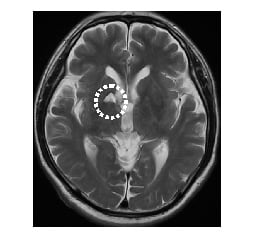

当センターの脳ドックで発見された脳および脳血管障害

• MRI画像

脳腫瘍

微小脳梗塞

脳梗塞

• MRA画像

左内頸動脈狭窄

脳動脈瘤